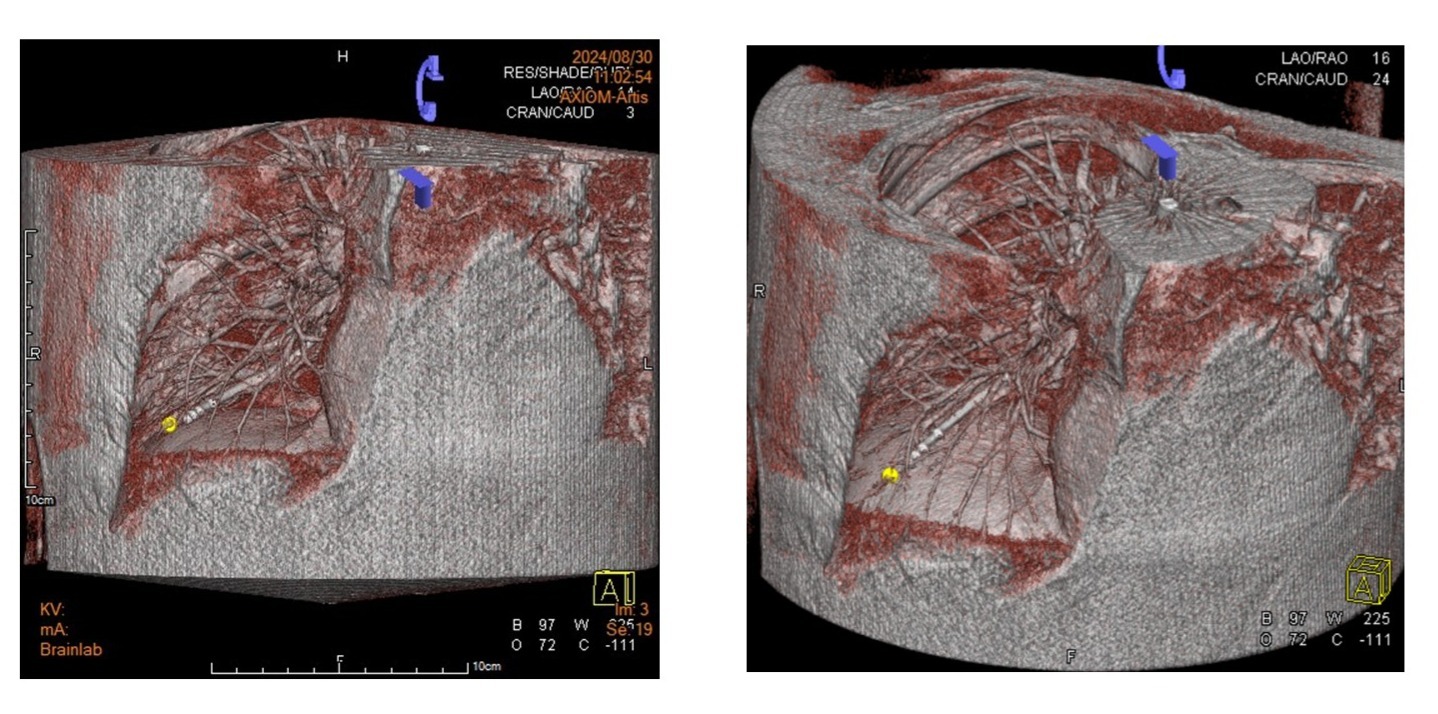

▲氣管鏡導航過程中以錐狀束電腦斷層掃描(Cone Beam Computed Tomography) 3D重組技術, 精確定位病灶